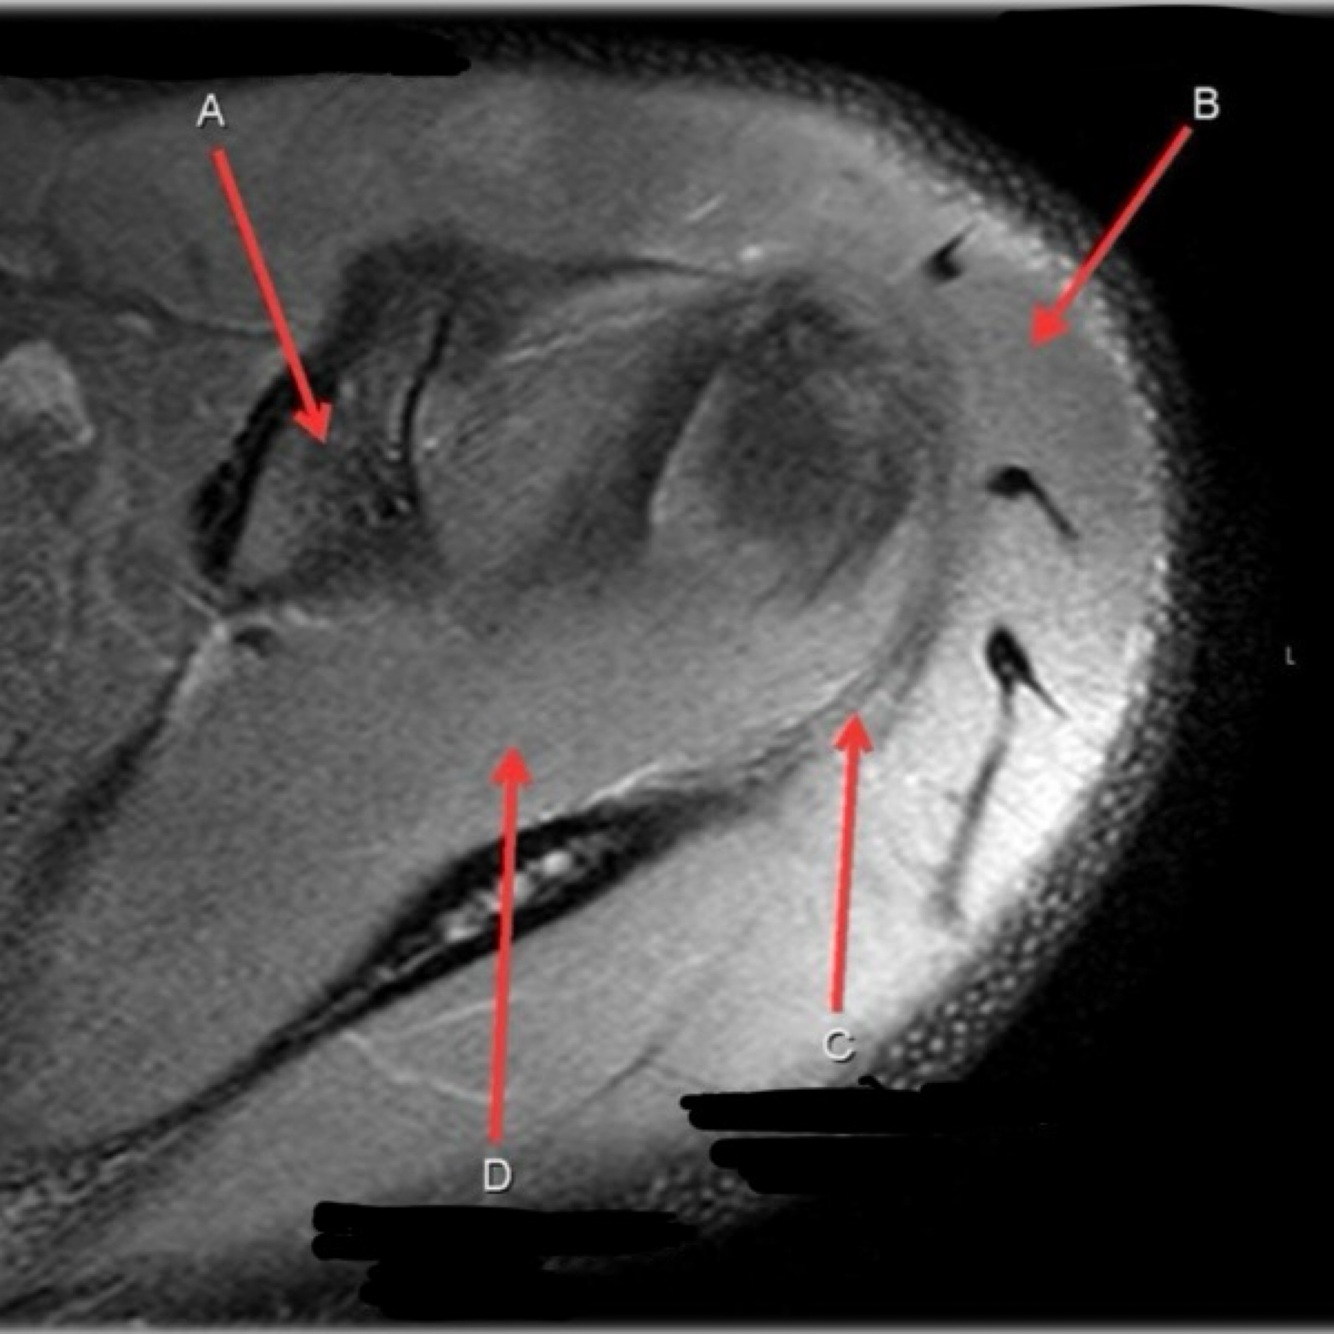

5

Perfectly

12

Q

What is letter B?

A

BICEPS TENDON (LONG HEAD)

How well did you know this?

1

Not at all

2